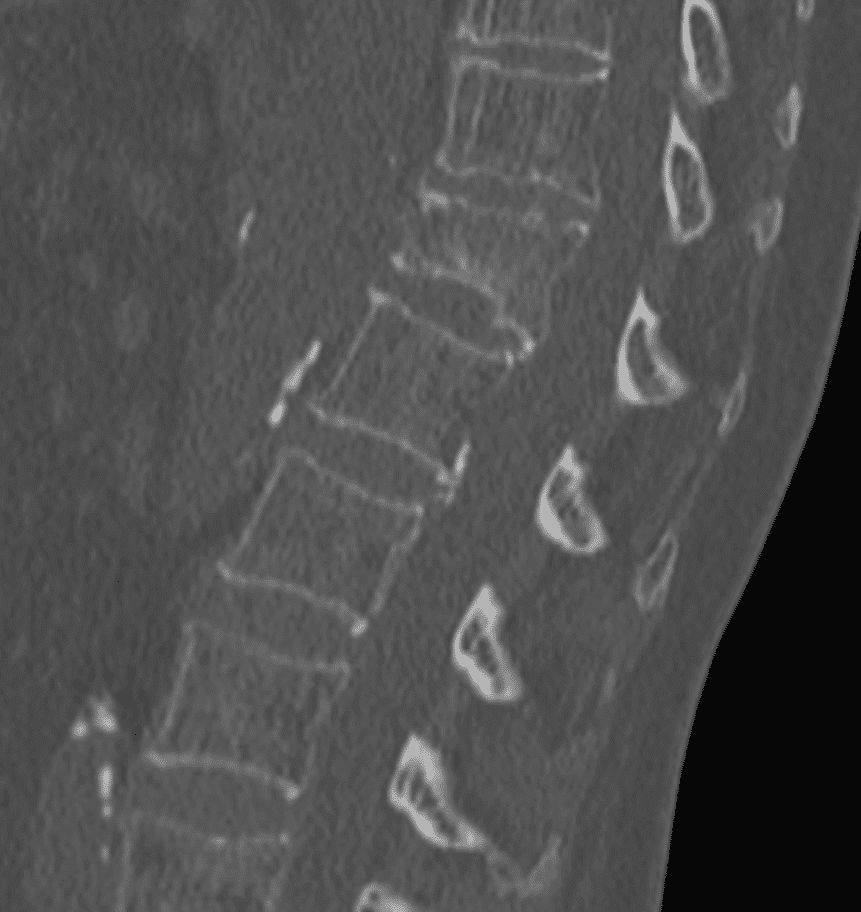

Guidage par imagerie

À l’aide de la fluoroscopie et/ou du scanner, l’équipe médicale guide avec précision une aiguille jusqu’au site de la fracture, en s’assurant d’éviter les structures sensibles.